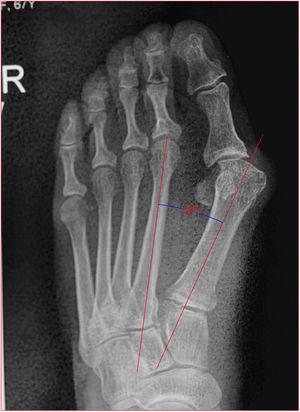

Desviación lateral del eje de alineación metatarso-falángico de 1er dedo.

Ángulo del Hallux 34° (VN <15°).

MEDIDAS RADIOGRAFICAS El Ángulo del Hallux Valgus (HVA) se forma por la intersección de los ejes longitudinales de la falange proximal y el primer metatarsiano. Un HVA es considerado normal si es menos de 15 grados.

El Ángulo Intermetatarsal 1o-2o (IMA) se forma por la intersección de los ejes longitudinales del primer y segundo metatarsaianos. Un IMA normal es considerado normal si es menor de 9 grados.

Angulo de valgo: es la intersección del ejes longitudinales del primer metatarsiano y de la falange proximal del hallux. Normal hasta 15 grados

Angulo intermetatarsiano

Es el ángulo entre los ejes longitudinales de primer y segundo metatarsiano, normalmente es menor de 12 grados, cuando esta aumentado se llama metatarso primo varo o aducto y deberá corregirse con osteotomía (fig. 9).